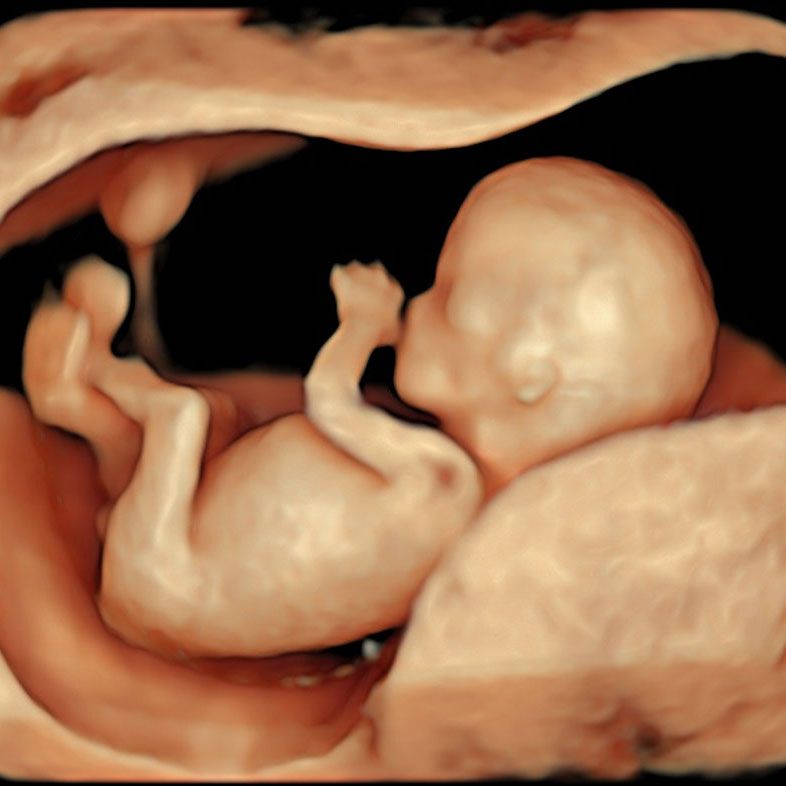

- 9-12. haftalarda dış genital organlar belirginleşmeye başlar.

- Ultrasonla net olarak ayırt edilebilmesi genellikle 18-21. haftalarda mümkün olur.